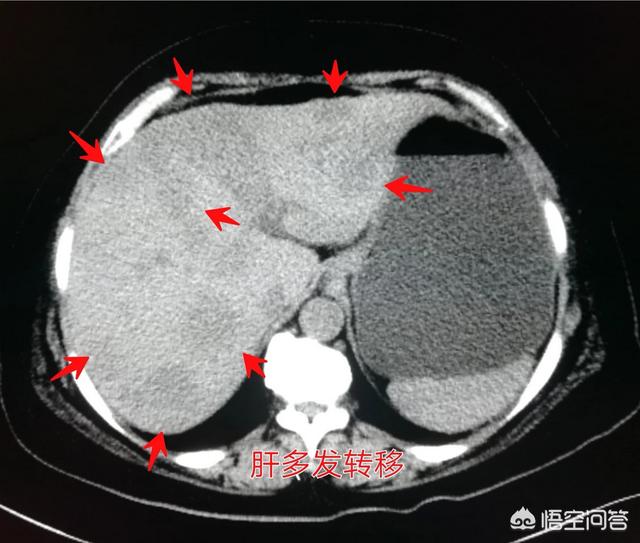

必须承认,某些终末期肝癌患者,治疗效果差比如那些肝脏弥漫性多发转移、门静脉瘤栓形成、全身条件差的病人,往往就缺乏有效的治疗手段了。

像这位病人,肝脏几乎长满了,并且有门静脉瘤栓,没有肝移植的条件。

这种情况只能对症处理,减少病人痛苦,做好临终关怀。